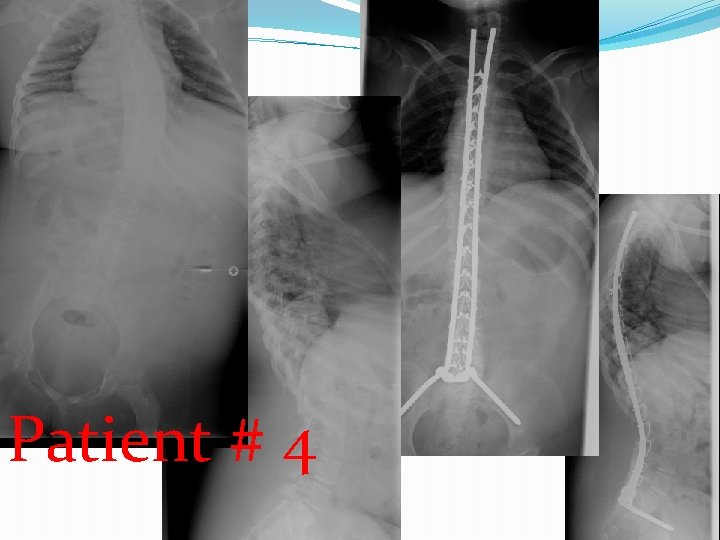

�At the time of surgery, two of these children were over 12 years of age and underwent posterior spinal arthrodesis with segmental spinal instrumentation from T 2 to pelvis. The other patients were under 10 years of age and were treated with spinal instrumentation in a growing rod construct, without arthrodesis. There were no complications from surgery with excellent sagittal and coronal correction of deformity obtained and maintained.

patient age at diagnosis (months) Age at Followsurgery up (months) months surgery Cobb pre-op Cobb post-op sagittal complica tions � #1 96 125 54 ** 54° 18° normal none � #2 96 148 25 *** 66° 53° normal none � #3 96 * 64° � #4 72 117 14 ** 42° 8° normal none � #5 24 154 14 *** 64° 4° normal none * normal • * Pending surgery • ** Segmental spinal instrumentation without arthrodesis • *** Segmental spinal instrumentation with arthrodesis

Patient # 4